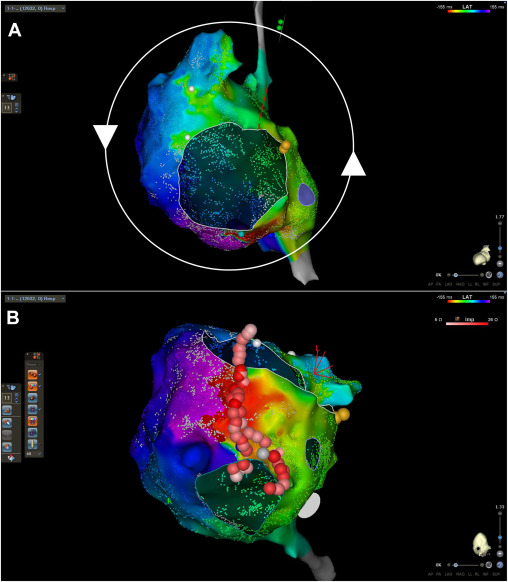

A truly collaborative, multidisciplinary effort with University of Pittsburgh colleagues to produce this manuscript on catheter ablation of macro-reentrant atrial tachycardia in adults with Ebstein anomaly. heartrhythmopen.com/article/S2666-…

Pulsed field ablation in persistent left superior vena cava for atrial fibrillation via interrupted inferior vena cava with azygos continuation utilizing novel electroanatomic mapping features in the presence of a permanent pacemaker Norman C. Wang, MD, MS heartrhythmcasereports.com/article/S2214-…

Pulsed field ablation in persistent left superior vena cava for atrial fibrillation via interrupted inferior vena cava with azygos continuation utilizing novel electroanatomic mapping features in the presence of a permanent pacemaker